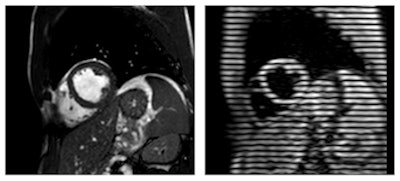

The study group compared baseline images with those obtained after one hour using cardiac MRI with complementary spatial modulation of magnetization (CSPAMM).

Cardiac MRI with CSPAMM revealed significantly increased peak strain and peak systolic strain rates, which reflect contractility, in the left ventricle. CSPAMM also showed that stroke volume -- the amount of blood pumped from the left ventricle -- increased after energy drink consumption due to the higher peak systolic strain.

Compared with baseline images, MRI with CSPAMM showed significantly increased peak strain and peak systolic strain rates in the left ventricle.